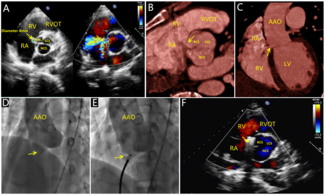

A 65-year-old woman with a past medical history of rheumatic heart disease underwent mechanical mitral and aortic valve replacements in 1992 followed by a 27-mm Epic tricuspid valve (Abbott) replacement in 2018 for treatment of severe...

A 65-year-old woman with a past...

09/05/2025

Giulia Passaniti, MD; Sahil Khera, MD, MPH; Rajeev R. Samtani, MD; Stamatios Lerakis, MD; Gilbert H.L. Tang, MD, MSc, MBA; Lucy M. Safi, DO